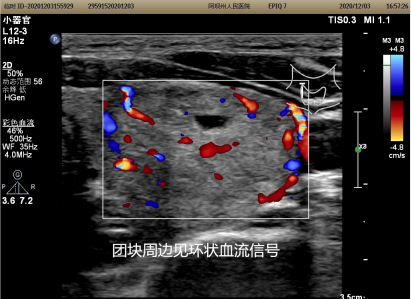

“感谢外二科的医生们给我做这个手术,脖子上一点疤都没有留。”40岁的李女士,因彩超发现左侧颈部包块4天于2020年12月7日入住州人民医院外二科,入院后经全面检查诊断为甲状腺左叶腺瘤(大小为22×2.6×3.7cm),传统开放的甲状腺包块摘除术无论是做横弧型切口还是“L”型切口都会留下非常长的疤痕,尤其是横弧型切口乍一看像是“自杀线”,很多女性患者,尤其是年轻女性患者会难以接受,李女士非常担心手术后会在脖子上留一道很长的疤痕并对手术很畏惧。术前,外二科的医师们大讨论为患者制定了详细的手术和治疗计划并给患者进行了详细的讲解,取得了患者的信任。